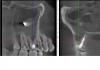

guest87 Опубликовано 31 марта, 2008 Поделиться Опубликовано 31 марта, 2008 Добрый день.У меня возникла следующая ситуация. Есть верхняя 6-ка, «вылеченная» порядка 13 лет назад. И затем трижды перепломбированная без переделки каналов. В принципе, она меня никак не беспокоит. В связи с возникновением ЛОР проблем был сделан снимок пазух и обнаружилось, что пломбировочный материал от зуба попал в гайморову пазуху + на зубе огромная киста. Снимок прилагается.По данному поводу была на консультации у двух хирургов-стоматологов.Один предлагает следующую схему лечения:1) Перепломбировать каналы и посмотреть динамику заживления – возможно это не киста, а гранулема и есть шансы спасти зуб2) В случае неудачи, резекция верхушки корня с кистой3) И если все совсем плохо – зуб удаляем, при возникновении соустья с пазухой делаем «заплаточку» Другой рекоммендует удалить зуб сразу как бесперспективный. При возникновении соустья все зашить + засыпать в образовавшееся отверстие от кисты костный материал. Собственно вопрос состоит в следующем:1) Действительно ли лучше удалить зуб и не мучиться?2) Можно ли ушить соустье без «заплатки»?3) Можно ли сразу в образовавшийся канал что либо засыпать и зашивать?4) Показана ли в данном случае последующая имплантация (учитывая ЛОР проблемы) или дождаться гибели соседних зубов и ставить мост? Ссылка на комментарий

DOK Elena Опубликовано 1 апреля, 2008 Поделиться Опубликовано 1 апреля, 2008 (изменено) Добрый день.У меня возникла следующая ситуация. Есть верхняя 6-ка, «вылеченная» порядка 13 лет назад. И затем трижды перепломбированная без переделки каналов. В принципе, она меня никак не беспокоит. В связи с возникновением ЛОР проблем был сделан снимок пазух и обнаружилось, что пломбировочный материал от зуба попал в гайморову пазуху + на зубе огромная киста. Снимок прилагается.По данному поводу была на консультации у двух хирургов-стоматологов.Один предлагает следующую схему лечения:1) Перепломбировать каналы и посмотреть динамику заживления – возможно это не киста, а гранулема и есть шансы спасти зуб2) В случае неудачи, резекция верхушки корня с кистой3) И если все совсем плохо – зуб удаляем, при возникновении соустья с пазухой делаем «заплаточку» Другой рекоммендует удалить зуб сразу как бесперспективный. При возникновении соустья все зашить + засыпать в образовавшееся отверстие от кисты костный материал. Собственно вопрос состоит в следующем:1) Действительно ли лучше удалить зуб и не мучиться?2) Можно ли ушить соустье без «заплатки»?3) Можно ли сразу в образовавшийся канал что либо засыпать и зашивать?4) Показана ли в данном случае последующая имплантация (учитывая ЛОР проблемы) или дождаться гибели соседних зубов и ставить мост?Добрый вечер ! Думаю. если Лор за Вас взялся, второй вариант более предпочтительный. Судя по снимку уже имея гайморит (возможно, что он вызван не только наличием материала в пазухе) вы можете нажить себе более серьезные проблемы. Надеясь на вторичное образование кости у верх. 6 , оставляете во рту мину, которая может взорваться в самую неподходящую минуту... В дороге,например,или на даче. или гайморит свой будете еще 100 лет лечить. Думаю стоит рассмотреть альтернативы замещения удаленного 6.Перелечивать дороже обойдется ...и морально, и материально.и спокойно спать будете. Изменено 1 апреля, 2008 пользователем DOK Elena Ссылка на комментарий